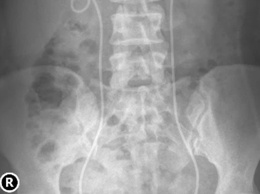

Hình ảnh thực tế và minh hoạ trường hợp tử cung đôi của sản phụ L.T.H.

Trong cuộc mổ, các bác sĩ phát hiện sản phụ có tử cung đôi, một dị dạng bẩm sinh hiếm gặp, tử cung không có thai đã chèn ép vào đoạn dưới của tử cung có thai, nguyên nhân khiến ngôi thai và cuộc chuyển dạ bất thường. Tuy nhiên, ca mổ đã diễn ra thuận lợi và đón chào một bé gái nặng 2800g, khỏe mạnh, khóc to, hồng hào ngay sau sinh.